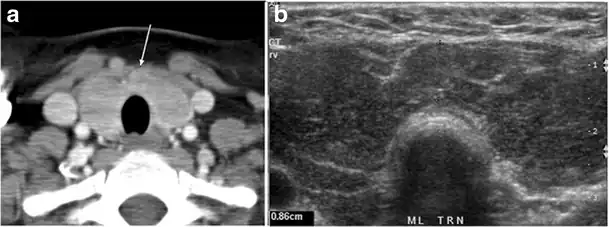

Fig. 7. A 51-year-old female patient post total thyroidectomy for PTC with elevated thyroglobulin measurement. an Axial non-enhanced CT scan of the neck at the level of the thyroid bed demonstrates a well-defined, rounded, homogenously dense soft tissue situated between the trachea and left internal jugular vein (white arrow). b Transverse ultrasound image of the neck demonstrates a well-defined, homogeneous, hypoechoic soft tissue nodule measuring 6 mm (white arrow) with no detected micro-calcifications. Biopsy showed a predominantly residual normal thyroid tissue with micro-foci of PTC.[1]